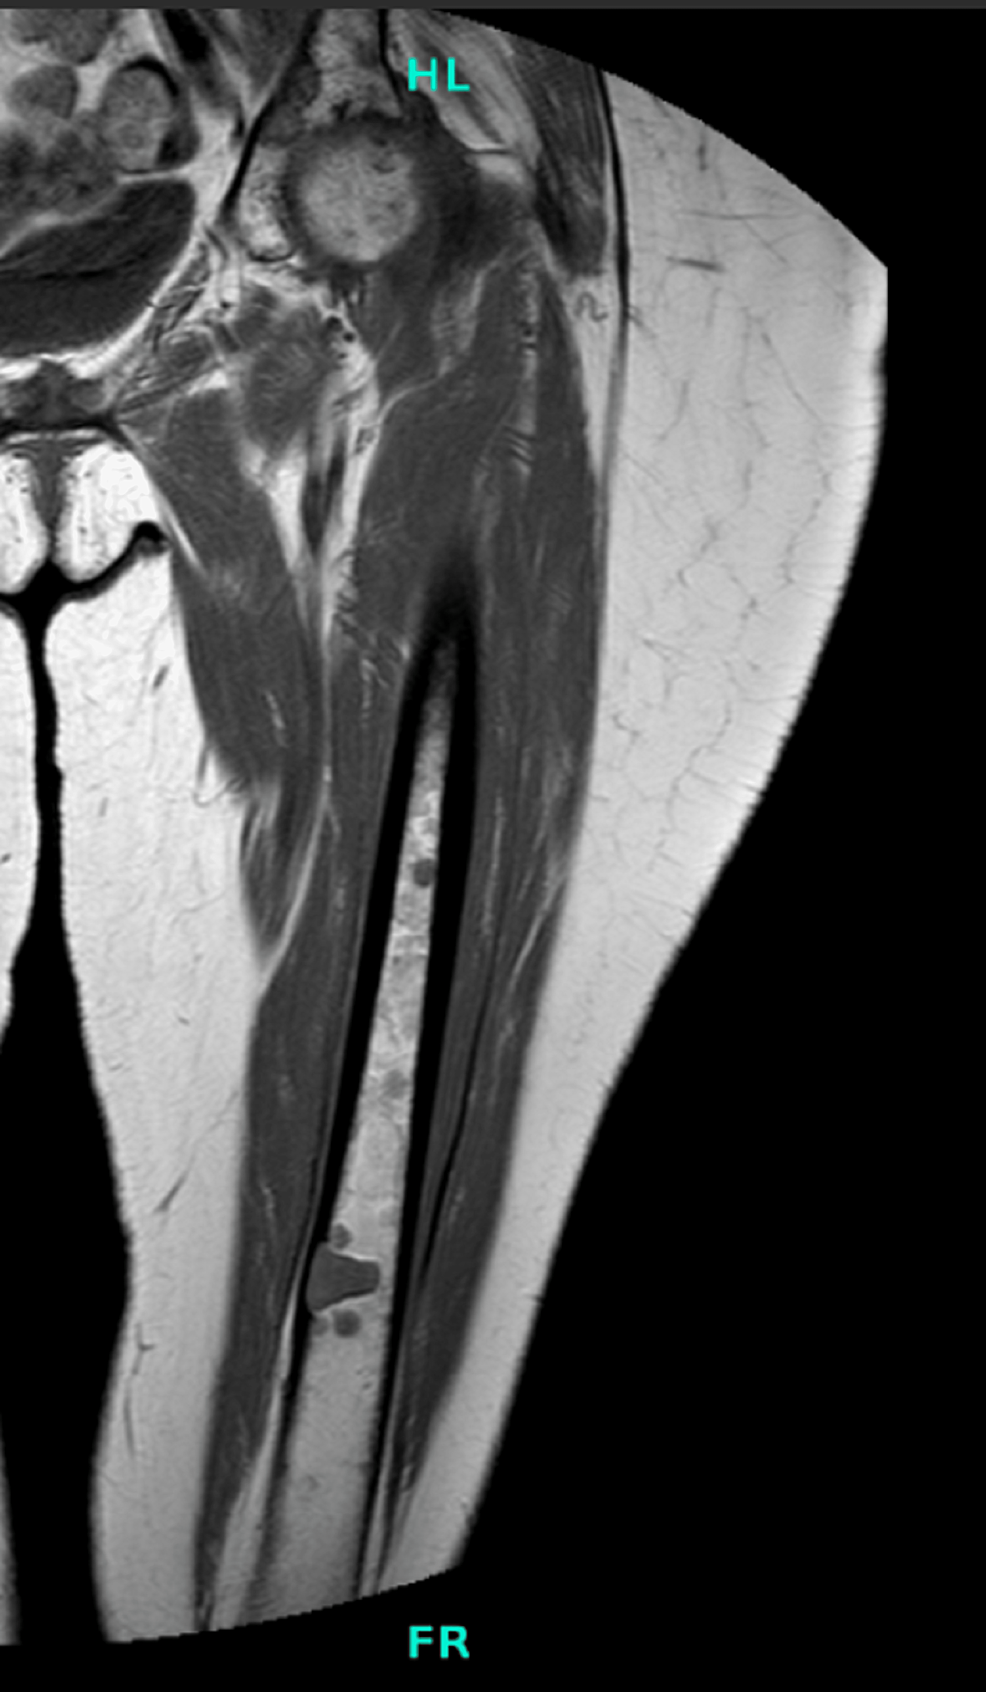

Figure 1 from Prophylactic Fixation of Impending Fractures Semantic Scholar What Is A Prophylactic Fixation in metastatic and/or primary bone tumors, prophylactic fixation of an upcoming fracture can significantly. prophylactic fixation can be done in a minimally invasive fashion. the aim is to evaluate and to highlight on value of prophylactic fixation of impending fractures in abnormal bone. prophylactic treatment before a fracture can improve patient quality of life, reduce pain. What Is A Prophylactic Fixation.